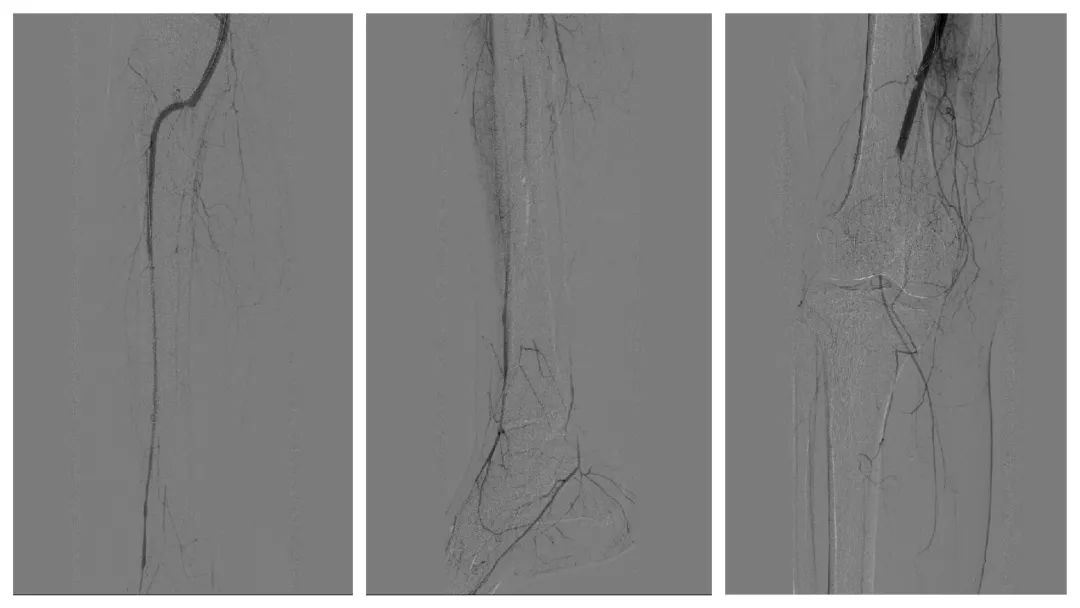

造影发现右股总静脉有附壁血栓,如施行常规右大腿根部股总静脉穿刺放滤器,有血栓被推走,患者在手术台上极有可能出现肺栓塞风险。病人同时患有右腘动脉栓塞也必须尽快取出。一条腿,动、静脉同时有血栓,上下位置还不同,这个病例的确给专家们出了一道难题。如果施行在高位穿刺髂外静脉,会因术后无法压迫,引起大出血,失血性休克;如果向下右腿股浅静脉穿刺放滤器,会因局部还要切开动脉取栓,无法压迫止血。刘洪主任凭借丰富的临床经验,决定同期手术“一口两用”。从右腿根部纵行切开,同时暴露股浅动、静脉。先经右股浅静脉小心向上穿刺,放滤器阻止血栓上行至肺部,避免发生致死性肺栓塞,并迅速缝合静脉;再向下穿刺右股浅动脉造影,用导丝双腔取栓导管反复多次操作,取出长度达15厘米,形状宛如一条“血蛇”的暗红色陈旧血栓。手术历时近4小时,术后肢体温度恢复,安返病房。